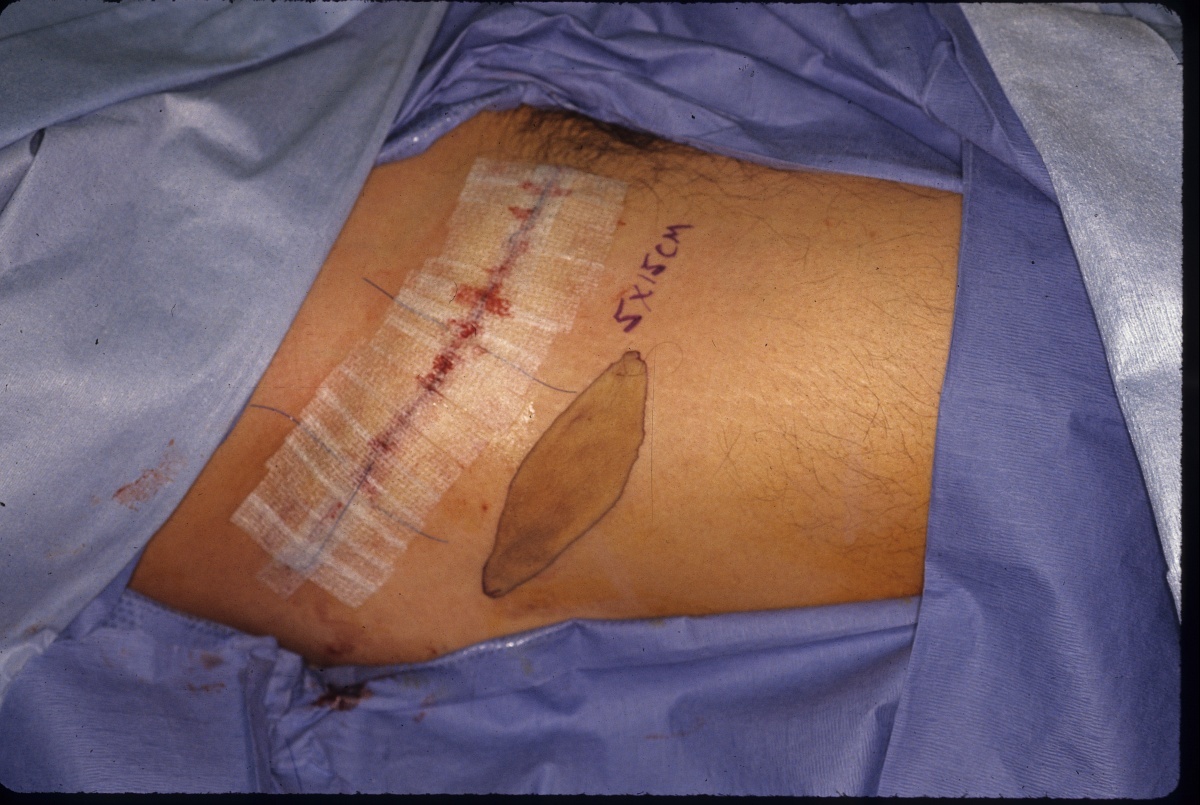

Case 2. Primary donor site closure 5X15 cm skin graft harvested from the inguinal crease.